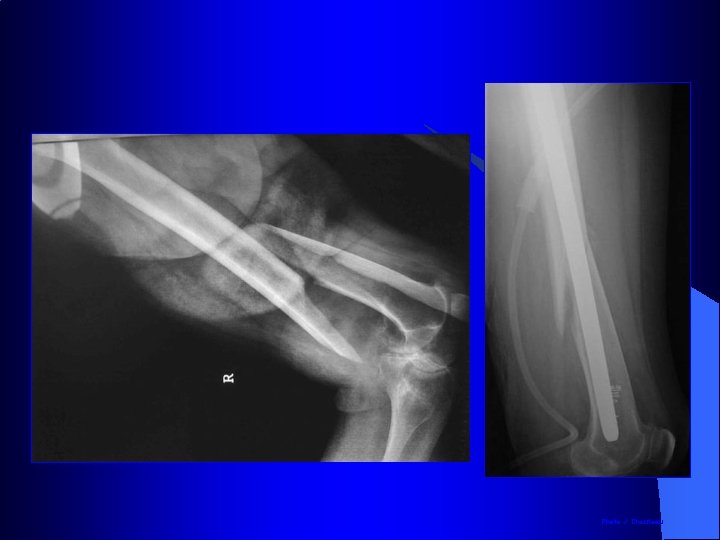

Enclouage rétrograde dans les fractures distales du fémur Introduction du clou par l’espace intercondylien dans le genou

Enclouage rétrograde dans les fractures comminutives distales du fémur

Enclouage à foyer fermé du tibia l l l Installation pour enclouage du tibia Table orthopédique Traction longitudinale Broche trans-calcanéenne ou étrier de Cunéo Genou fléchi Contrôle radioscopique de la réduction

Installation pour enclouage du tibia • Le canal médullaire est abordé en avant des épines tibiales • Introduction du guide puis des alésoires et enfin du clou